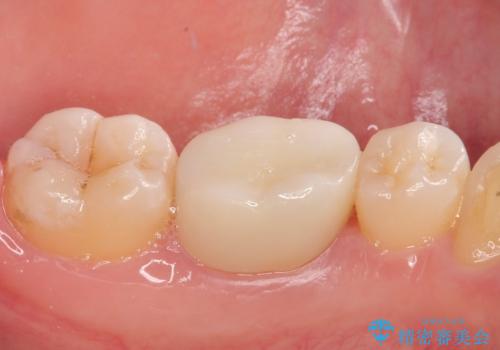

痛みやしみることもなく、適合もよく、機能的に問題もなく、見た目も満足されていました。

今後は他の金属の詰め物(メタルインレー)のところを治療していく予定です。